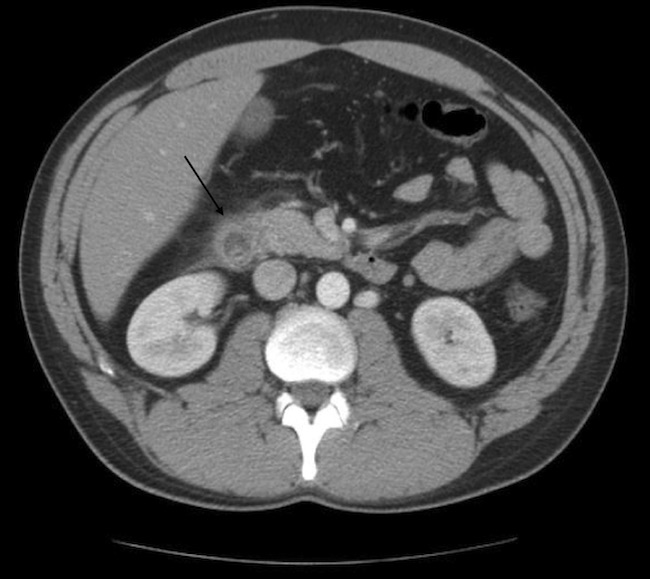

Diagnostic tests. Laboratory findings were pertinent for mildly elevated lipase (682 U/L), mild hypertriglyceridemia (170 mg/dL), and normal calcium. Abdomen ultrasonography showed no signs of cholecystitis or cholelithiasis. Computed tomography (CT) scan of abdomen showed duodenal inflammation (Figure 1).

Figure 1. CT scan of the abdomen on day 0 showing an inflamed duodenum (arrow).